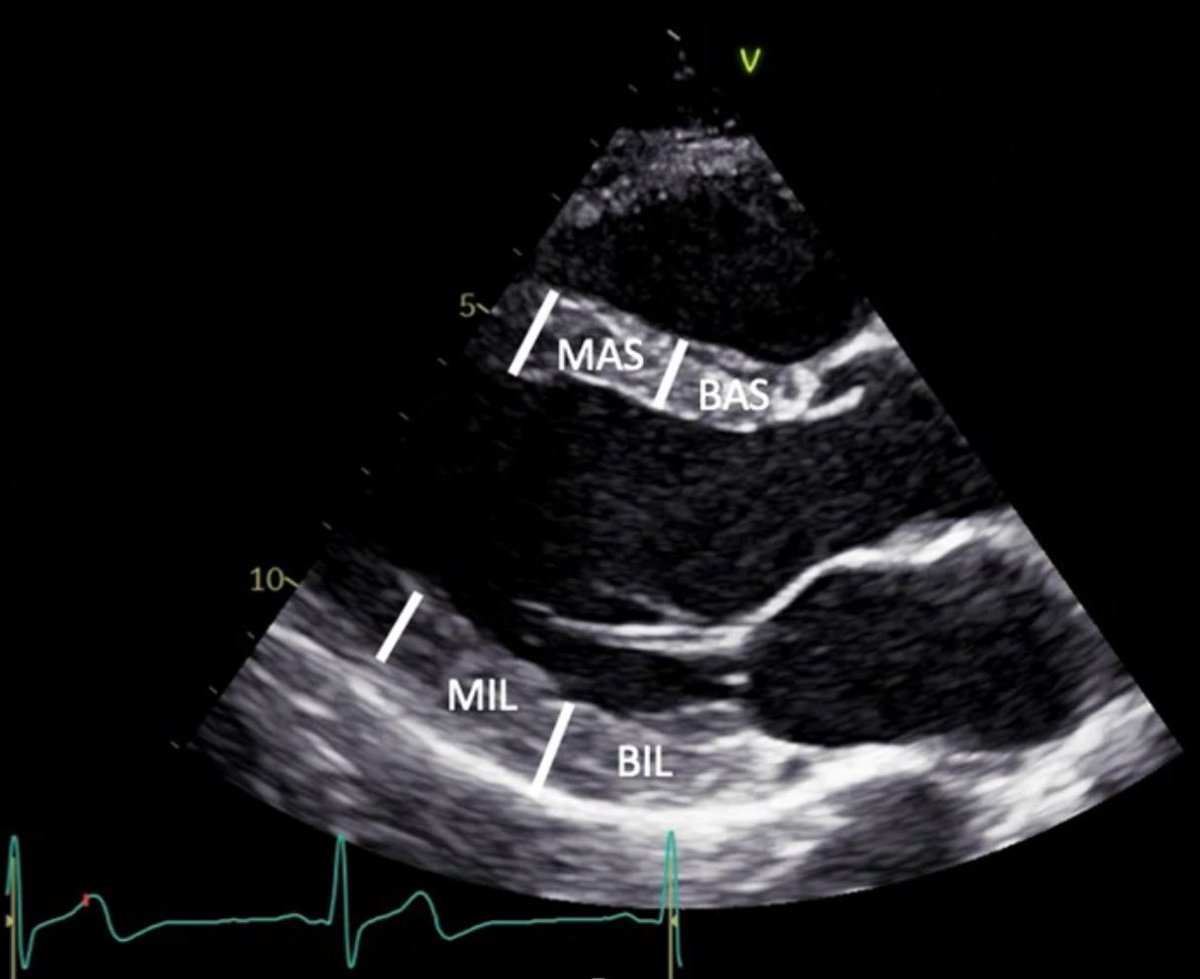

#firstecho #MedEd #POCUS from @BSEcho BAS: Basal antero-septum MAS: Mid antero-septum BIL: Basal infero-lateral MIL: Mid infero-lateral

POCUSpeek's tweet image. #firstecho #MedEd #POCUS from @BSEcho

BAS: Basal antero-septum

MAS: Mid antero-septum

BIL: Basal infero-lateral

MIL: Mid infero-lateral